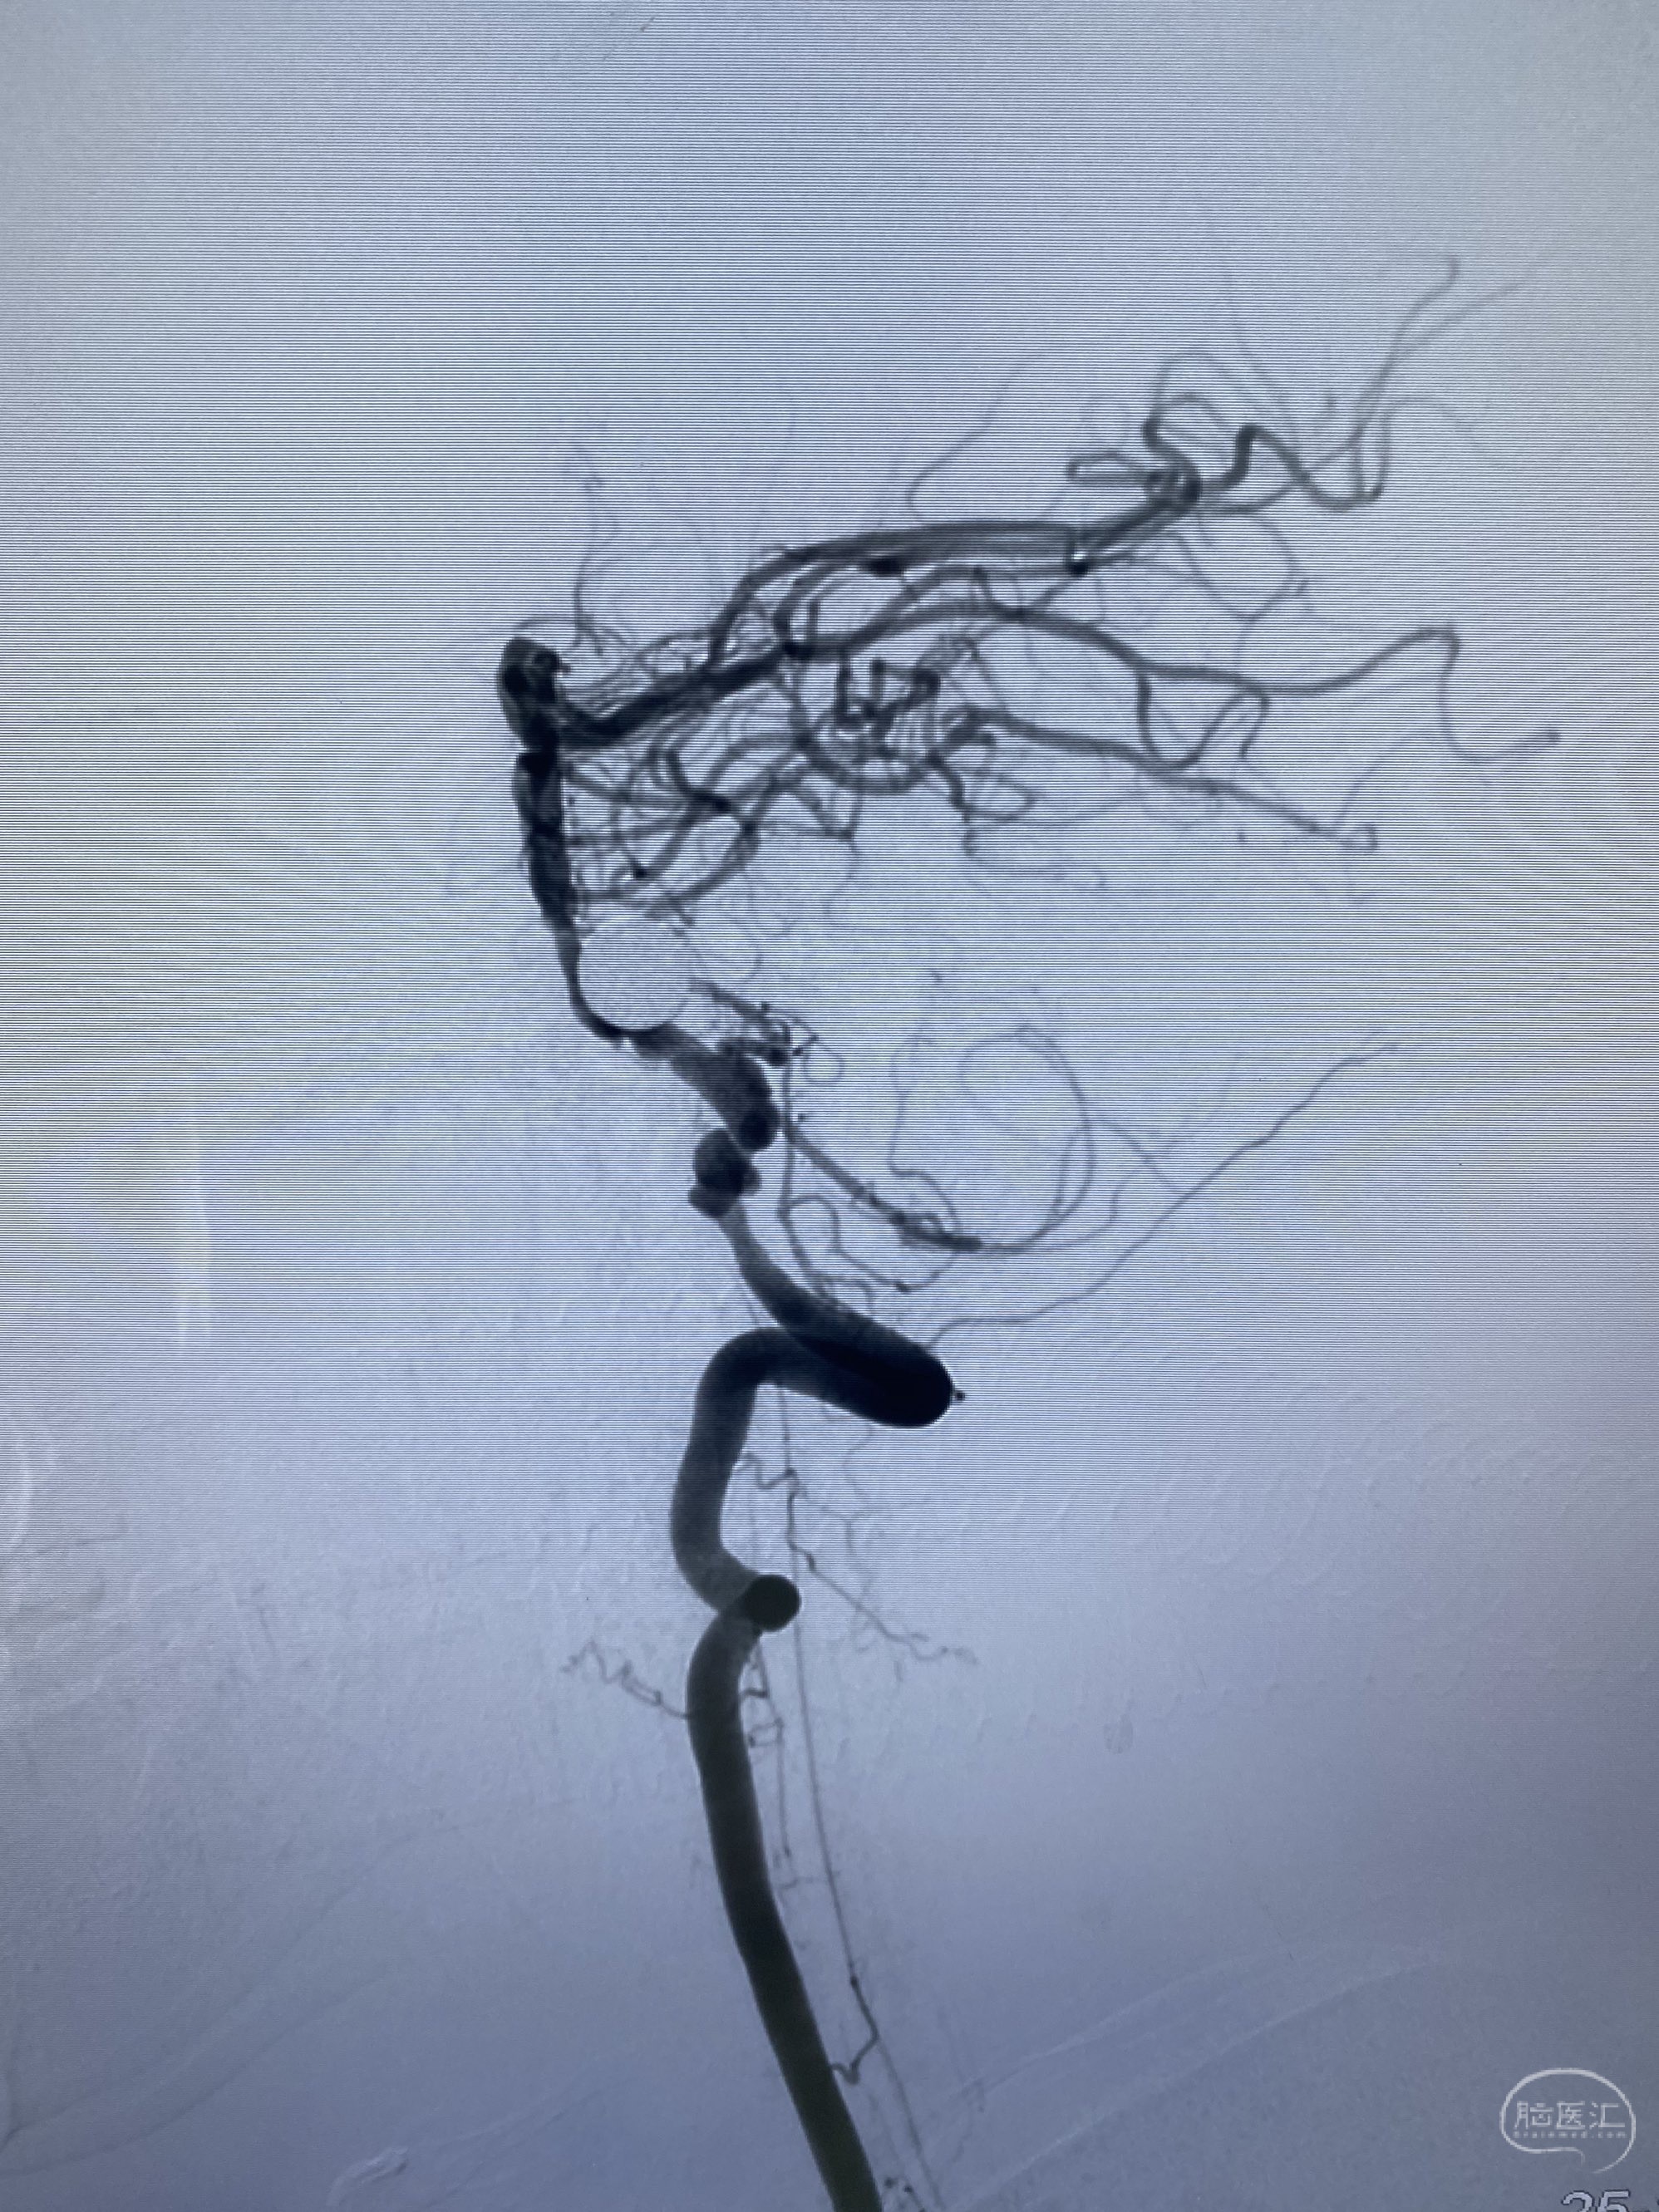

今日手术,TJG,M62Y,一期左侧颈动脉狭窄支架植入,二期椎动脉V4段多发夹层动脉瘤伴狭窄,常规支架辅助栓塞方法复杂又危险,血流导向装置植入快捷又安全。南阳市中心医院神经内科脑血管病介入团队pipeline flexFD植入两人导师资格。

椎动脉颅内段多发夹层动脉瘤伴载瘤动脉狭窄pipeline flex植入

今日手术,TJG,M62Y,一期左侧颈动脉狭窄支架植入,二期椎动脉V4段多发夹层动脉瘤伴狭窄,常规支架辅助栓塞方法复杂又危险,血流导向装置植入快捷又安全。南阳市中心医院神经内科脑血管病介入团队pipeline flexFD植入两人导师资格。